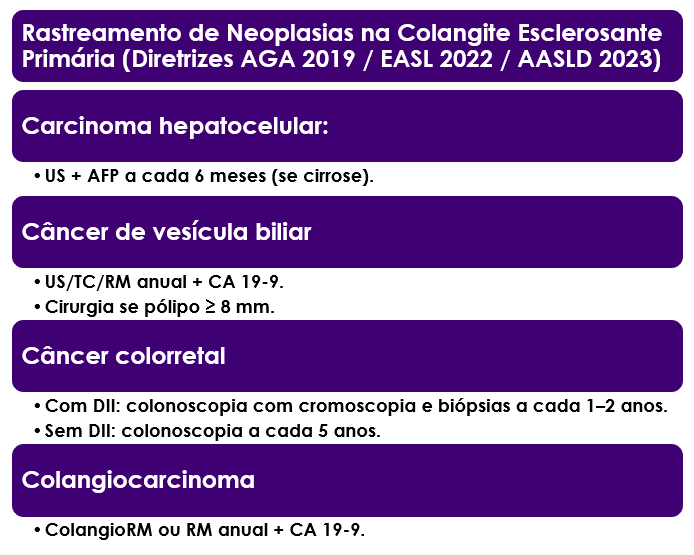

Um destaque muito importante em relação às complicações da CEP é o risco de desenvolvimento de câncer. O risco de câncer das vias biliares é muito aumentado, sendo responsável por 32% dos óbitos nos portadores da CEP. O risco de câncer do intestino é mais alto, particularmente quando a doença vem acompanhada de doença inflamatória intestinal, sendo responsável por 8% dos óbitos. Apenas 18% dos portradores acabam falecendo por insuficiência hepática, e 9% por complicações pós transplante. Por esse motivo, é fundamental realizar exames periódicos para rastreamento desses cânceres.